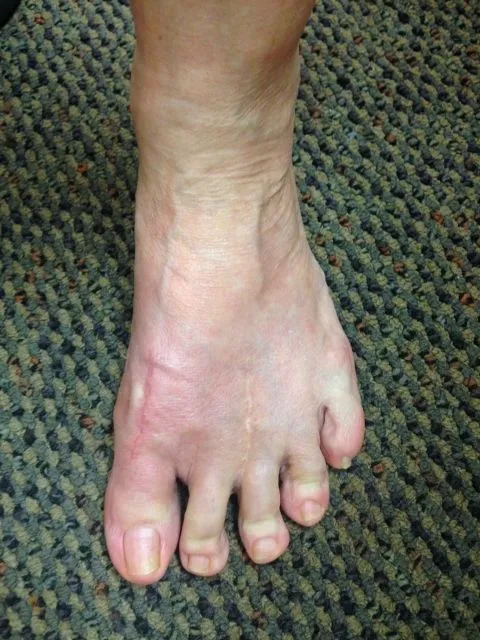

Before and immediately postop S/P bunionectomy

Before and 6 months status post bunionectomy.